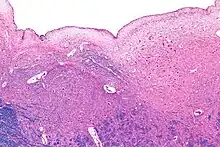

Micrograph of the posterior portion of the open part of the medulla oblongata, showing the fourth ventricle (top of image) and the hypoglossal nucleus (medial - left of image) and the dorsal motor nucleus of the vagus nerve (lateral - right of image). H&E-LFB stain.

- Hypoglossal nucleus (XII) - motor

- Dorsal motor nucleus of vagus nerve (X) - visceromotor